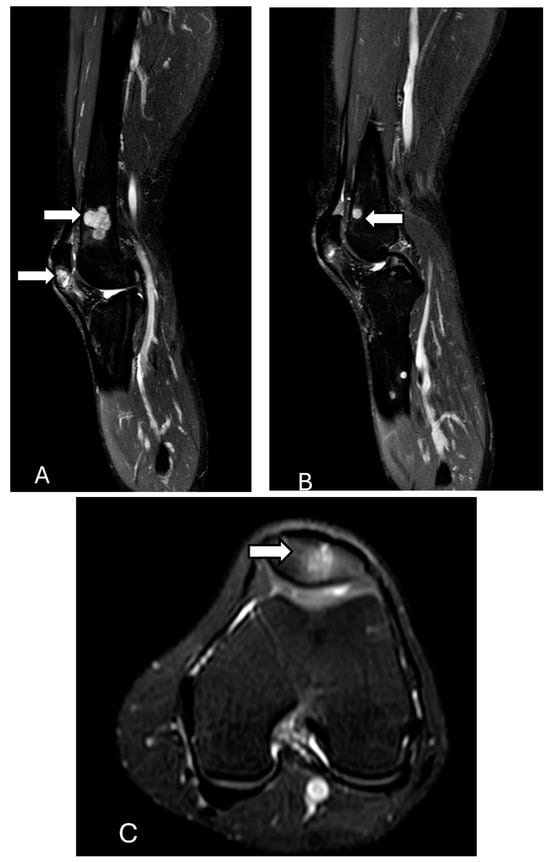

3.10. Metabolic Diseases